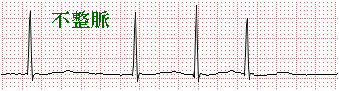

(1)心電図

心筋が興奮すると活動電流が発生する。 このような  心筋の電気的変化を波形にし、記録したものです。 この検査では、不整脈や狭心症、心筋梗塞、心室肥大、電解質異常、その他様々な情報を知ることができます。